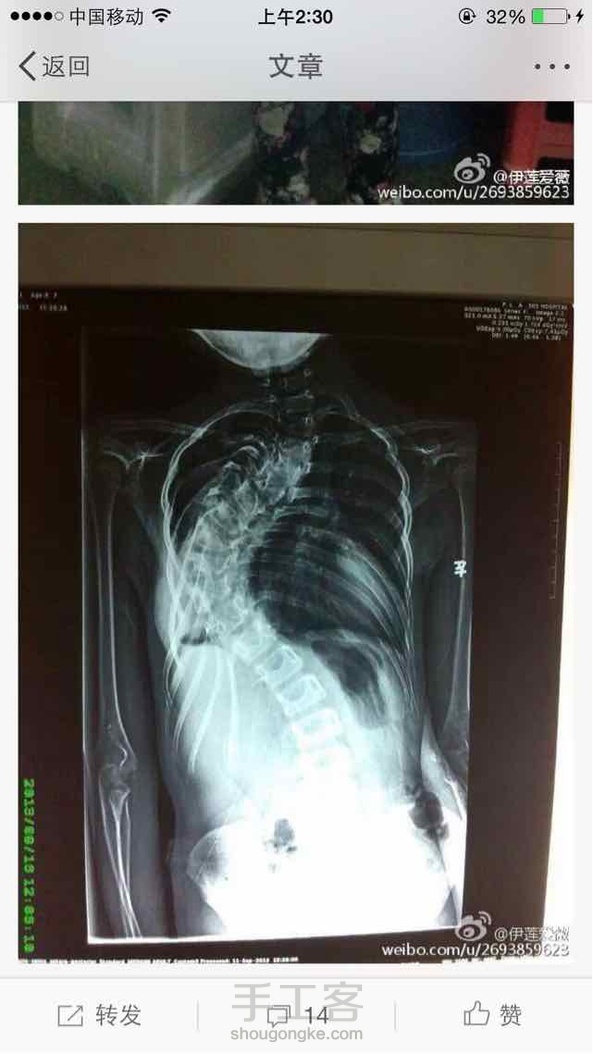

脊柱严重弯曲的婷婷,再不手术,就面临瘫痪,为了筹集手术费,自己做手工花卖,今天有个爱心花店教婷婷插花,有没有特别漂亮。